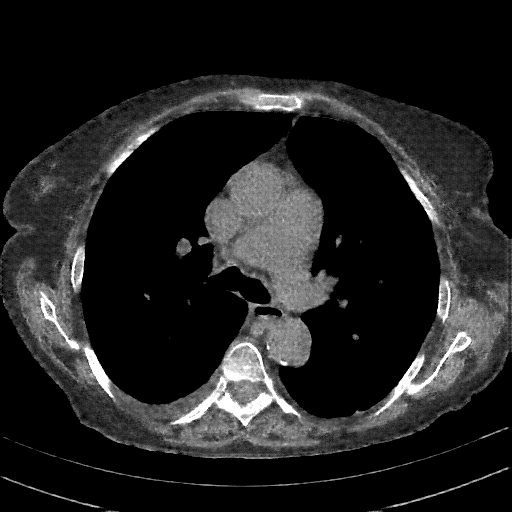

Targeted Slice 70 - Mediastinum Window Analysis (Generated vs Real Venous)

0.625

Mediastinum SSIM

56.4

Mediastinum RMSE

25.0

Mediastinum MAE

Average Mediastinum Window Metrics Across All Slices (153 slices) - Generated vs Real Venous

0.556

Mediastinum SSIM (Avg)

58.5

Mediastinum RMSE (Avg)

29.2

Mediastinum MAE (Avg)

Original VENOUS CT scan

Mediastinum window (WL 40, WW 400 β†’ Low βˆ’160, High +240)